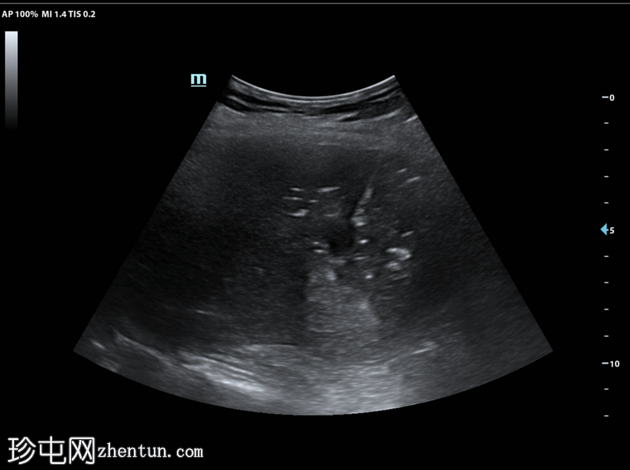

超声检查

3.png

泌尿系统

肝脏第6和第7段可见多个高回声气体腔,遮挡肝脏后部

肝脏其他部位形态及回声纹理正常

胆总管扩张,无结石,肝内胆管未见扩张

其他方面正常无游离液体

超声表现符合气肿性肝脓肿。数小时后进行的肝脏增强 CT 多期扫描显示气肿性肝脓肿破裂。